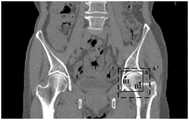

FIG. 4 is a schematic diagram of a bone joint segmentation method applied to bone joint segmentation of a medical image according to an embodiment of the present invention;

Fig. 4 is a schematic diagram of a bone joint segmentation method applied to bone joint segmentation of a medical image according to an embodiment of the present invention. Referring to fig. 4, a two-dimensional schematic diagram of a bone joint segmentation method applied to bone joint segmentation in a femoral head CT image is shown, in which a solid line frame a represents a bone joint positioning frame regressed according to each sampling point in the femoral head CT image and a random forest positioning model; point B1 and point B2 represent at least a first seed point selected within the bone joint location box; iterative difference threshold growing is performed based on points B1 and B2 within a preset range of the bone joint location box, i.e., within a dashed box a', so that segmentation of the femoral skull joint cortex can be performed.